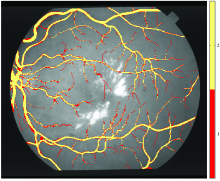

Retinal blood vessels The STructured Analysis of the Retina (STARE) dataset was used in this case study. The dataset consists of twenty colour retinal images, which for the purposes of this study are treated as a single image ( and ). An example image is presented in Figure 1d. A mask was formed which delineates the pixels that fall outside the retina by thesholding the intensity of the red channel at a value of (the black area) and these pixels were excluded from the experiments. The dataset contains two annotations which delineate the blood vessels in the image.

The pixel-level annotator agreements for each case study are presented in Figure 2. To verify that these are acceptable for experimental use Smyth’s lower error bound estimate, i.e. the average error rate amongst the annotators, was calculated and found to be (Segmentation), (Fissure), (Landslide), and (Blood Vessel). These values are well within the limit that is recommended [33] and considerably lower than the error bound of found in the volcano labelling experiment presented by the author [33], in which the signal-to-noise ratio of the features is much lower than in the presented case studies.

The ratio of pixels having a minimum level of annotator agreement to the number of pixels that belong to annotated regions is presented in Figure 3. For the Segmentation, Fissure and Blood Vessel case studies the ratio decreases approximately exponentially as a function of minimum annotator agreement. For the Fissure dataset the thirteen annotators agree on only approximately of all of the pixels that were marked as fissures by any of the annotators. The ratio decreases most rapidly in the Segmentation case study, whereas the Landslide case study exhibits a rather linear trend. These differences are due to a combination of the geometric structure of the targeted objects, and the fact that disagreement tends to occur along object borders. As such, uncertainties in the outline of a feature lead to a stronger disagreement if the targeted features are only one pixel wide (Segmentation) or several pixels wide (Fissure, Blood Vessel) when compared to the rather blob-like regions exhibited in the Landslide case study. Indeed, if the outlines of the Landslide annotations are analysed, agreement also drops approximately exponentially.